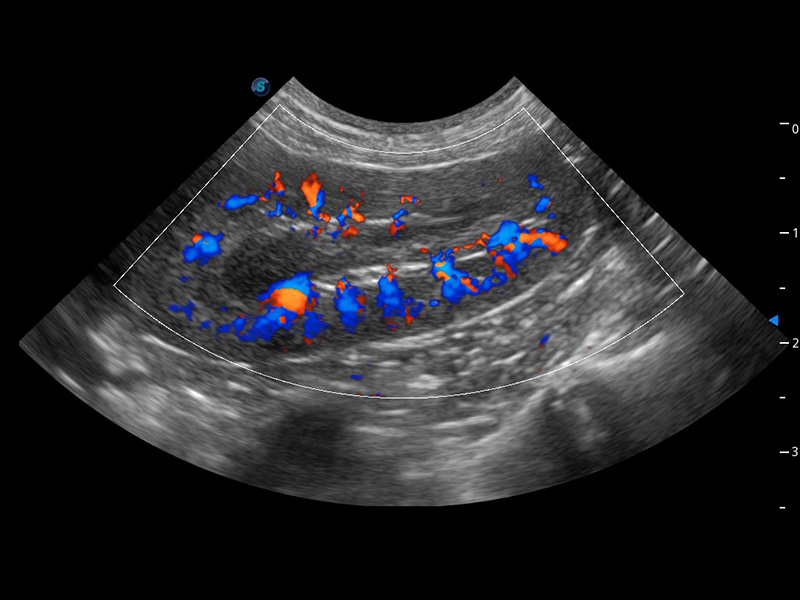

ProPet 60 作为一款高端台式动物超声设备,为动物医生的日常诊断提供了一系列贴合动物临床需求、解决临床实际问题的高级成像功能。凭借全系列高清探头,满足医生对腹部、心脏、生殖、浅表、肌骨等成像的所有需求,切实帮助您提升检查效率,提高诊断信心。

兽用彩色多普勒超声诊断系统

动物是人类最亲密的朋友和最值得信赖的伙伴。新葡的京集团8814检测站也一直致力于探索动物专用的超声影像解决方案。 全新推出的ProPet系列,是新葡的京集团8814检测站在动物超声影像智能化、专业化、精准化的一次跨越式革新。动物不能用言语来表述自己的不适,通过超声影像,ProPet系列搭建了动物医生与不同物种沟通的“桥梁”,为动物医生注入了“治愈之力”。